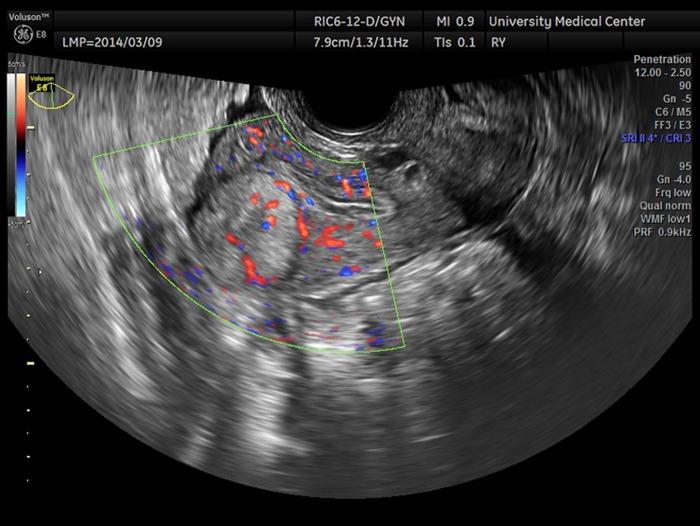

Adenomatoid uterine tumors are rare, and their appearance on medical imaging modalities is not well established. We present a case of an adenomatoid uterine tumor reviewing a unique sonographic presentation, magnetic resonance imaging (MRI), gross surgical appearance of the tumor, and microscopic pathology images. A 29-year-old gravida 0 Caucasian woman presented with dysmenorrhea, menorrhagia, and desire to conceive. Transvaginal ultrasound revealed a 2.7 cm round, well-circumscribed posterior intramural uterine mass. The mass was hyperechoic centrally with a thin hypoechoic rim. Color Doppler imaging revealed a prominent vascular rim around the periphery of the mass as well as central vascularity not typical for a leiomyoma. MRI, with and without intravenous gadolinium, was obtained showing a 2.7 cm posterior fundal mildly enhancing uterine mass suggestive of leiomyoma. The mass had a heterogeneous signal pattern on T2-weighted images, and no fat component was noted within the mass. Repeat transvaginal ultrasound showed interval growth of the mass to 3.5 cm with a lipomatous appearance. Adenomatoid uterine tumors are rare and may be mistaken for uterine leiomyomata. Unique features include sonographic appearance of central hyperechogenicity with a hypoechoic rim and prominent peripheral and central vascularity in conjunction with MRI revealing a heterogeneous signal pattern on T2-weighted images without fat component. Gross surgical appearance reveals a nondiscrete capsule and secretion of mucoid material when the mass is exposed. We present a case of adenomatoid tumor providing sonographic, MRI, surgical, and pathological correlation. The patient subsequently conceived spontaneously and delivered at term by cesarean section. The patient underwent a preoperative evaluation with complete blood count, comprehensive metabolic panel, blood type with antibody screen, and pregnancy test. She underwent laparoscopic excision with robotic assistance for removal of the tumor. Grossly, the uterine mass had a very soft consistency atypical for a uterine leiomyoma making dissection more challenging. During dissection the mass diffusely secreted a mucoid material although the capsule was not disrupted. The lesion was excised intact and was removed from the peritoneal cavity in an endocatch bag without internal morcellation. Microscopic examination revealed an adenomatoid tumor.

腺肌瘤样子宫肿瘤较为罕见,其在医学影像检查中的表现尚未完全明确。我们报告一例腺肌瘤样子宫肿瘤,回顾其独特的超声表现、磁共振成像(MRI)、肿瘤的大体手术外观及微观病理图像。一名29岁未孕的白人女性,因痛经、月经过多及有生育意愿前来就诊。经阴道超声检查发现一个2.7厘米圆形、边界清晰的子宫肌壁间后壁肿物。肿物中央呈高回声,周边有一薄层低回声边缘。彩色多普勒成像显示肿物周边有明显的血管环,且中央有血管分布,这并非平滑肌瘤的典型表现。行MRI检查,静脉注射钆对比剂前后成像显示一个2.7厘米的子宫底部后壁轻度强化肿物,提示为平滑肌瘤。该肿物在T2加权图像上信号不均匀,且肿物内未发现脂肪成分。再次经阴道超声检查显示肿物增大至3.5厘米,呈脂肪瘤样外观。腺肌瘤样子宫肿瘤较为罕见,可能被误诊为子宫平滑肌瘤。其独特特征包括超声表现为中央高回声、周边低回声边缘及明显的周边和中央血管分布,同时MRI显示T2加权图像上信号不均匀且无脂肪成分。大体手术外观显示肿物无明显包膜,肿物暴露时可见黏液样物质分泌。我们报告一例腺肌瘤样肿瘤,提供超声、MRI、手术及病理的相关性。患者随后自然受孕并足月剖宫产分娩。患者术前进行了全血细胞计数、综合代谢指标检测、血型及抗体筛查和妊娠试验等评估。她在机器人辅助下行腹腔镜肿瘤切除术。大体上,子宫肿物质地非常软,这与子宫平滑肌瘤不同,增加了手术分离的难度。手术分离过程中,肿物弥漫性分泌黏液样物质,尽管包膜未破裂。病变完整切除,装入内套袋从腹腔取出,未进行内部碎解。显微镜检查显示为腺肌瘤样肿瘤。